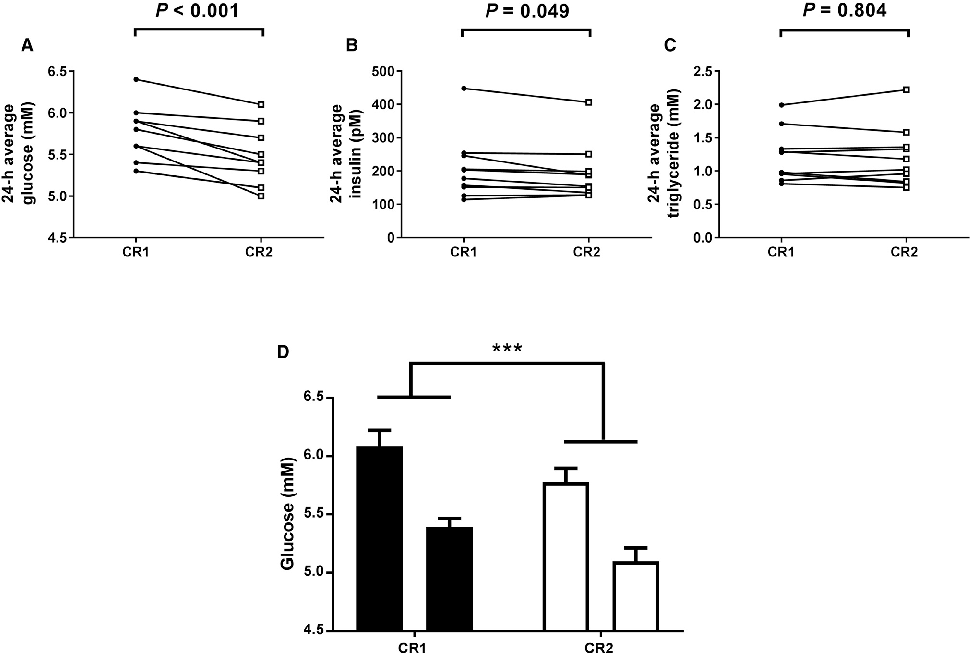

Average plasma glucose concentration under constant routine conditions is reduced following a 5-hour delay in meal times, suggesting meal timing significantly influences glucose metabolism rhythms.

Meal Timing Regulates the Human Circadian System.

Plasma glucose concentrations during constant routine conditions show a significant reduction after participants experienced delayed meal times, indicating that meal scheduling influences circadian glucose regulation.

Meal Timing Regulates the Human Circadian System.